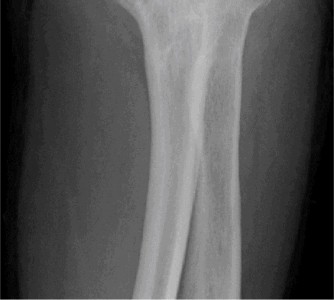

- Standard Radiographs: AP, lateral, and oblique views are crucial for assessing joint space narrowing, osteophyte burden (anterior coronoid, posterior olecranon, radial head), subchondral sclerosis, and the presence of loose bodies. Weight-bearing views are not typically used for the elbow.

- Computed Tomography (CT) Scan: Highly valuable for complex OA, especially post-traumatic cases. Provides detailed information on bone morphology, the size and location of osteophytes, quantification of loose bodies, and assessment of bone stock for potential arthroplasty. 3D reconstructions are extremely helpful for visualizing complex deformities and planning osteophyte excision or implant placement.